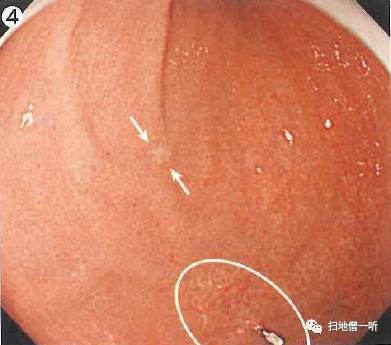

A:胃癌在图1。HP未感染胃癌。

背景粘膜光滑,轻微水肿状的RAC不甚清晰,未见明确的萎缩肠化,HP感染不明。胃窦小弯有褪色粘膜,性质难以判断,周围粘膜没有明确的萎缩像,单发褪色性病变怀疑印戒细胞癌。

NBI非扩大像显示周边粘膜为褐色

靛胭脂染色后色调变化模糊,胃小区未见明确变化,病变边界不清。提示癌性病变在粘膜表层未显露,提示该病变可能位于粘膜中层。

最终诊断:胃窦小弯,O-IIb,6mm,sig,T1a(M),UL(-)

小结:铺路石状的粘膜存在使HP判断比较困难

HP未感染病例应寻找褪色性病变

补充:粘膜整体呈轻度水肿状态,皱襞之间可见大小不等的半球状多发隆起,和周围粘膜相同色泽。此称为“铺路石状粘膜”,所见隆起部分粘膜增厚而使RAC不明。本病例为HP未感染。铺路石状粘膜使HP的判断较为困难,常考虑PPI所致。